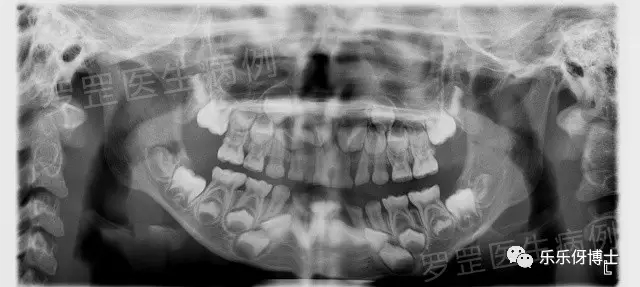

2.拍片

(口腔全景片)

如果家长选择了某种情势,医森初诊当天会安排助手给小朋友拍摄口腔全景片&头颅侧位片,可以更加准确了解小朋友牙齿生长发育情况及骨骼发展情况,以便更好制定正畸方案。